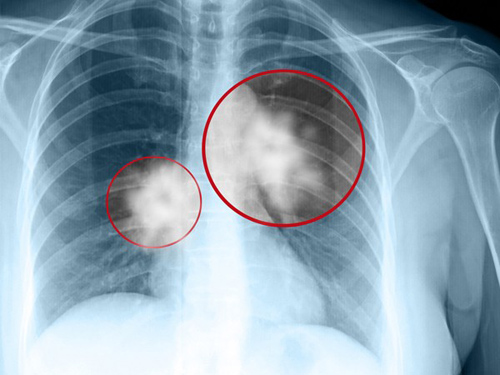

+ Tầm soát ung thư phổi: Ngoài việc thay đổi lối sống lành mạnh, vẫn nên tầm soát ung thư phổi định kỳ, đặc biệt là người hút thuốc lá lâu năm, người trên 40 tuổi, người có tiền sử gia đình mắc ung thư phổi… Các phương pháp chụp CT liều thấp, X-quang, xét nghiệm máu… có thể phát hiện ung thư phổi từ giai đoạn sớm, khi người bệnh chưa có triệu chứng. Điều trị ngay ở giai đoạn đầu sẽ mang lại hiệu quả cao hơn và tăng cơ hội sống cho bệnh nhân.